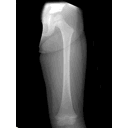

femur.png

GolpesenElMuslodelNino.jpg